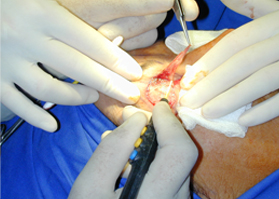

適合于皮下組織的切割和剝離。

特別是在運(yùn)血較為豐富的部位。

適用于良好控制的止血。

適合于要求良好止血的切割。